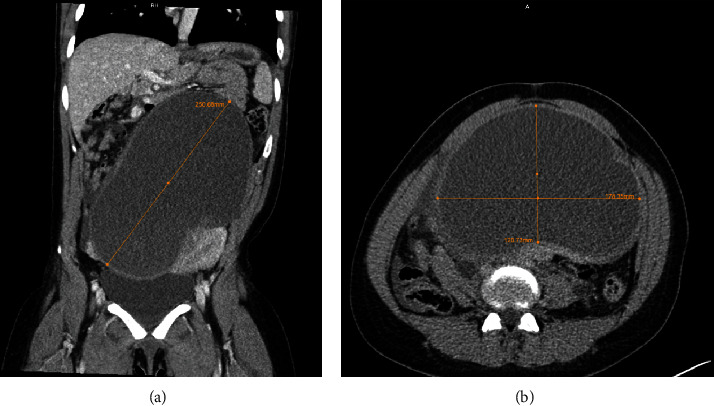

子宫内膜异位症是育龄妇女常见的妇科疾病,其症状多种多样,如盆腔疼痛、月经过多、痛经、排便困难和不孕。子宫内膜异位症是子宫内膜异位症的一种,其特征是囊性肿块,最常见于卵巢。本病例讨论的是一个罕见的 25 厘米子宫内膜异位症患者的治疗方法,该患者之前未确诊为子宫内膜异位症,因急性高血压急诊入院。据认为,巨大的囊肿对肾脏血管造成了肿块效应,引发了新血管性高血压,需要立即进行干预。该病例采用微创手术切除囊肿并溶解粘连,术后未出现并发症。

Endometriosis is a common gynecological condition in women of reproductive age and has variable symptomology such as pelvic pain, menorrhagia, dysmenorrhea, dyspareunia, and infertility. Endometriomas are a form of endometriosis and are characterized by cystic masses most commonly found on the ovaries. This case discusses the management of a rare occurrence of a 25-cm endometrioma in a patient without a prior diagnosis of endometriosis, who presented to the emergency room in an acute hypertensive emergency. It is believed that the large cyst caused a mass effect against renal vasculature precipitating renovascular hypertension that required immediate intervention. This case was approached with minimally invasive surgical removal of the cyst and lysis of adhesions without postoperative complications.